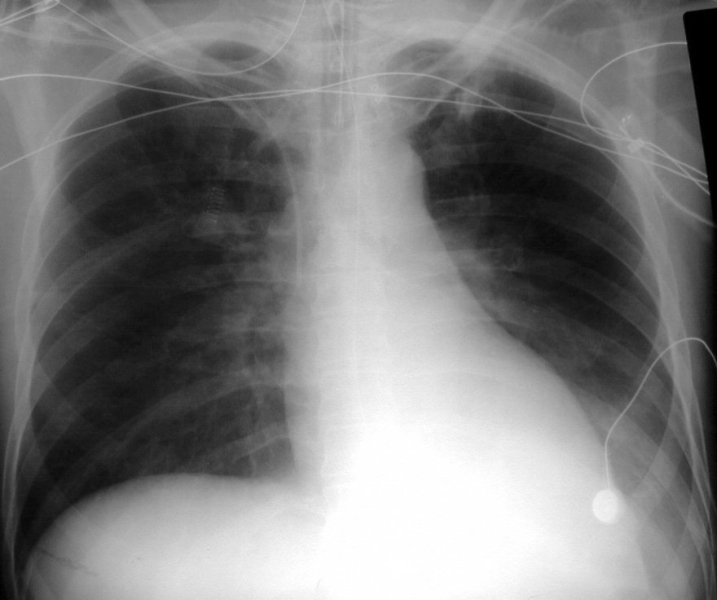

What’s going in in this CXR?

This is a postpneumonectomy patient, with the surgical clips in place.

This was taken POD1 following pneumonectomy. Over the next months, this space will slowly fill with fluid, and then over the following 3 months it will gradually fibrose. The heart and mediastinum will then shift towards this side due to myofibroblast contraction.

The patient will also be missing the 5th or 6th rib, taken as part of the procedure, and surgical clips will be present.